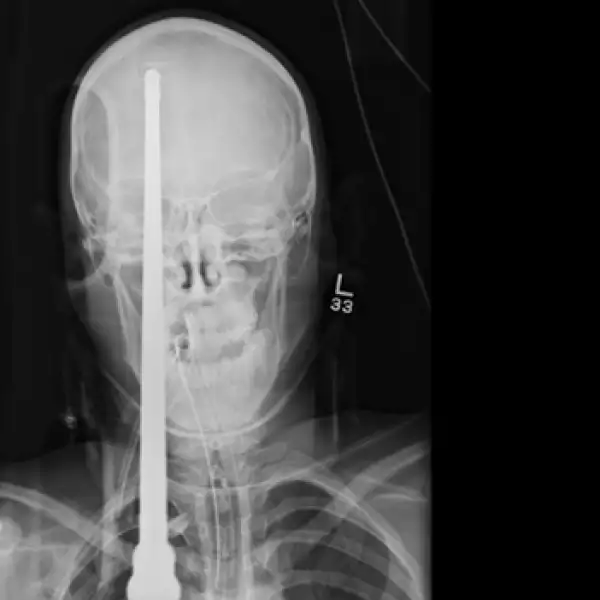

Un joven sobrevive luego de que un arpón de pesca atravesara su cráneo

Yasser López, logró sobrevivir después de que su amigo le disparara accidentalmente un arpón en un lago de Florida